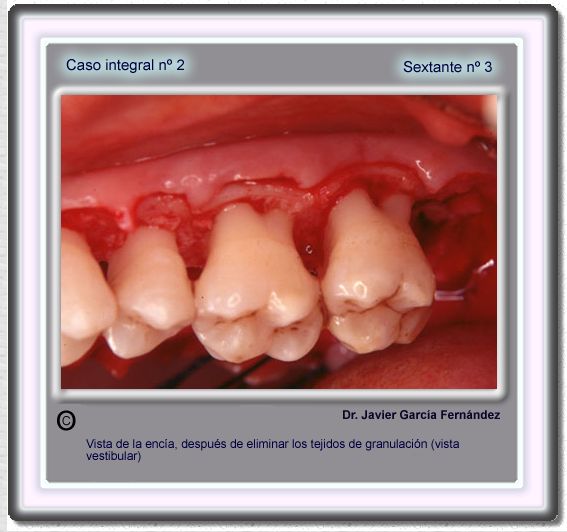

image 41